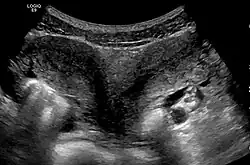

Ultrasound showing didelphys